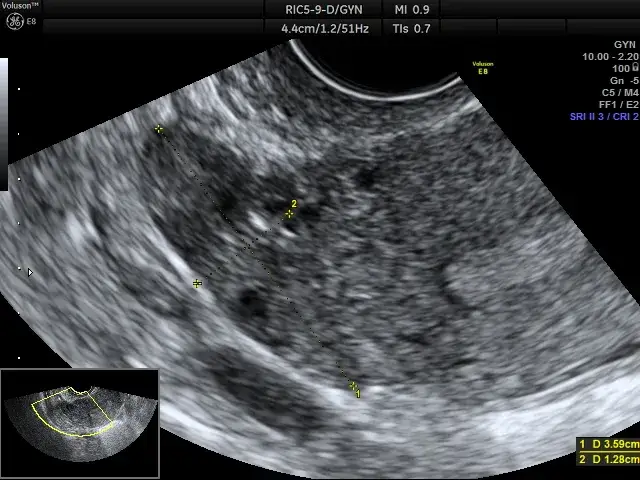

Pęcherzyk Graafa to niewielka struktura w jajniku, która zawiera niedojrzałą komórkę jajową. W każdym cyklu miesiączkowym, pod wpływem hormonów, jeden z pęcherzyków staje się "dominujący" i zaczyna intensywnie rosnąć. Jego główną rolą jest doprowadzenie komórki jajowej do pełnej dojrzałości, a następnie jej uwolnienie podczas owulacji. Kiedy badanie USG wykazuje pęcherzyk o wielkości 18 mm, jest to dla nas, lekarzy, bardzo ważna informacja. Oznacza to, że pęcherzyk jest już na zaawansowanym etapie dojrzewania i zbliża się do optymalnej wielkości do pęknięcia, która zazwyczaj mieści się w zakresie 18-26 mm.

Pęcherzyk 18 mm jest już dojrzały, ale nie oznacza to, że pęknie natychmiast. Uważa się, że pęcherzyk jest dojrzały i gotowy do pęknięcia, gdy osiąga wielkość od 18 do 26 mm. Z mojego doświadczenia wynika, że wielu specjalistów przyjmuje, że pęcherzyk pęka najczęściej przy wielkości 20-24 mm. To daje nam pewien zakres, a dokładny moment zależy od indywidualnych predyspozycji i sygnałów hormonalnych.

Często skupiamy się na pęcherzyku, ale równie ważna jest grubość i struktura endometrium, czyli błony śluzowej macicy. To właśnie w endometrium zagnieżdża się zarodek. Aby implantacja była możliwa, endometrium w momencie owulacji powinno mieć co najmniej 7-8 mm grubości i mieć charakterystyczny, trójliniowy wygląd w obrazie USG. To świadczy o jego prawidłowym przygotowaniu do przyjęcia zarodka. Bez odpowiednio przygotowanego endometrium, nawet idealna komórka jajowa i plemnik mogą nie dać rady.